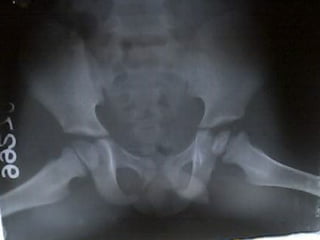

Investigations

X-ray – AP

Frog leg lateral view

( contraindicated when

suspecting acute slip)